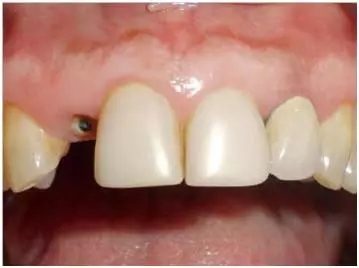

口內(nèi)檢查(圖1至4);

圖1:外傷9天后的臨床檢查:12牙牙冠在釉牙骨質(zhì)界水平處折斷。部分折斷面被牙齦覆蓋,可以看到中央有折斷的金屬根樁(鈦)。11和21牙由復(fù)合樹脂貼面修復(fù),22牙由金屬烤瓷冠修復(fù)。